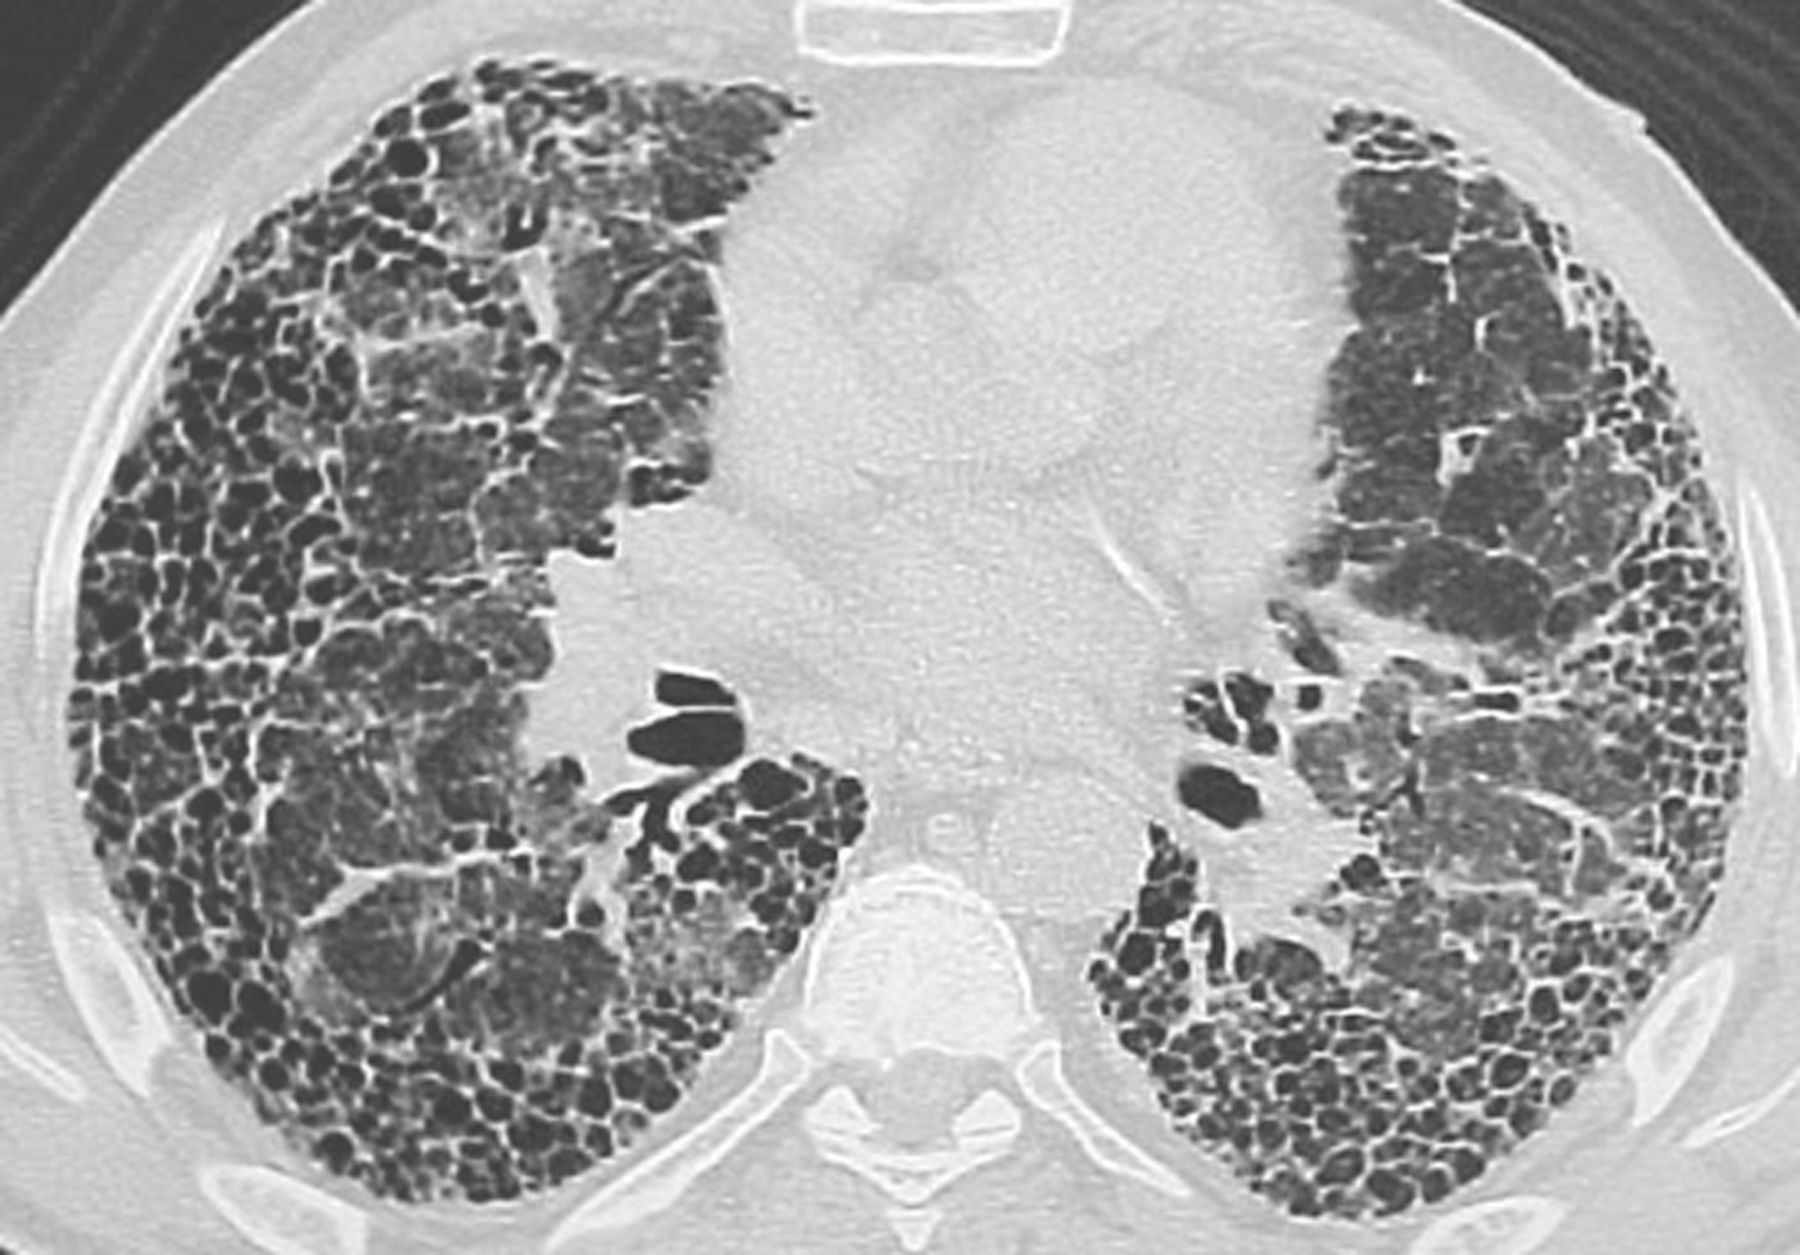

Pulmonary fibrosis hay Xơ phổi là một bệnh nghiêm trọng gây sẹo tiến triển của mô phổi. Xơ hóa phổi gây trở ngại cho chức năng phổi và gây oxy thấp trong máu. Có nhiều nguyên nhân gây ra sự hình thành Sẹo (xơ hóa) trong phổi bao gồm: phản ứng quá mẫn (một loại nghiêm trọng của phản ứng dị ứng), Sarcoidosis, Wegener Granulomatosis, Lupus, Viêm khớp dạng thấp, viêm nhiễm, tác nhân môi trường (Amiăng, Silica, tiếp xúc với loại khí nhất định), tiếp xúc với bức xạ ion hóa (như xạ trị để điều trị ung thư), và một số thuốc (Nitrofurantoin, Methotrexate). Trường hợp không có nguyên nhân của xơ hóa được xác định gọi là "xơ hóa phổi tự phát".

Xơ phổi là một bệnh nghiêm trọng gây sẹo tiến triển của mô phổi. Chứng xơ phổi bắt đầu với chấn thương lặp đi lặp lại ở các mô trong và giữa các túi khí nhỏ (phế nang) trong phổi, cuối cùng dẫn đến sẹo (xơ hóa), làm cho hơi thở khó khăn. Các triệu chứng thông thường nhất là khó thở và ho khan.